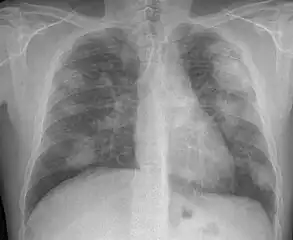

For uncomplicated silicosis, chest x-ray will confirm the presence of small (< 10 mm) nodules in the lungs, especially in the upper lung zones. Using the ILO classification system, these are of profusion 1/0 or greater and shape/size "p", "q", or "r". Lung zone involvement and profusion increases with disease progression. In advanced cases of silicosis, large opacity (> 1 cm) occurs from coalescence of small opacities, particularly in the upper lung zones. With retraction of the lung tissue, there is compensatory emphysema. Enlargement of the hilum is common with chronic and accelerated silicosis. In about 5–10% of cases, the nodes will calcify circumferentially, producing so-called "eggshell" calcification. This finding is not pathognomonic (diagnostic) of silicosis. In some cases, the pulmonary nodules may also become calcified.

Chest X-ray showing uncomplicated silicosis -